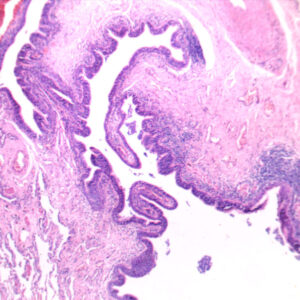

The Pathology teaching slides we offer are professionally hand-mounted, accurately stained, and individually labeled. Our microscope pathology slides are great for medical students, It has an excellent introduction to human disease in microscopy. The Pathology teaching slides are cover-slipped and preserved in cedarwood oil. All slides are carefully labeled for easy reference and are arranged in a fine plastic box with a separator. This pathology teaching slide set includes 14 systems of human diseases. It is excellent for educational use and is perfect for all levels of medical student study including home school programs.

What’s included in this 100pcs pathology teaching slides set: